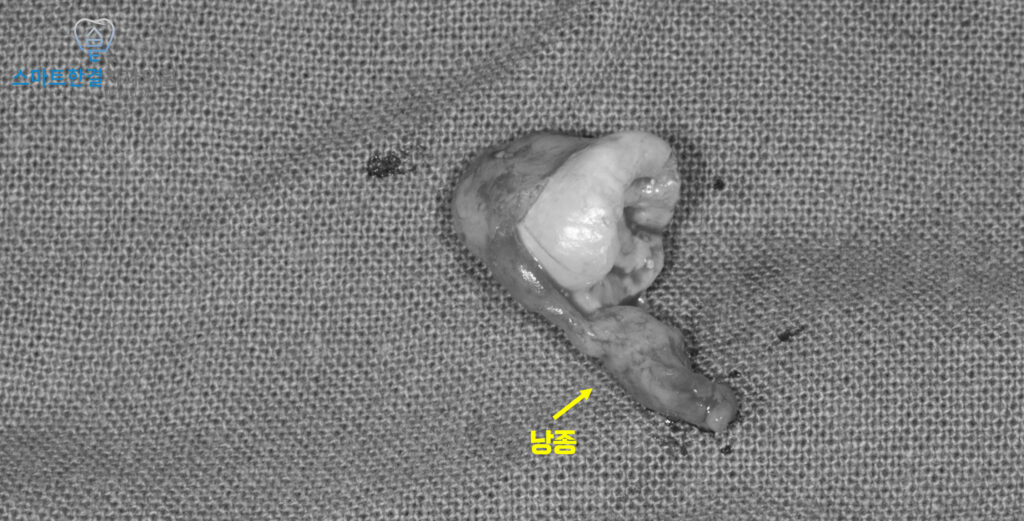

<사랑니 발치 및 낭종 적출>

매복 사랑니 발치를 위해 잇몸을 절개한 후,

주변 치조골을 일부 삭제하여

사랑니가 보이도록 접근했어요.

위쪽 사랑니의 경우 아래 사랑니와 달리

치아 분할 없이도 비교적 원활하게

발치가 가능한 경우가 많아,

해당 환자분 또한 치아 분할 과정 없이

안정적으로 발치를 진행했답니다.

사랑니 뿌리에 낭종이 함께 딸려나온 것을

확인할 수 있었으며,

이는 낭종이 해당 매복 사랑니와

직접적으로 연관되어 형성된 병소였음을

보여주는 소견이었어요.